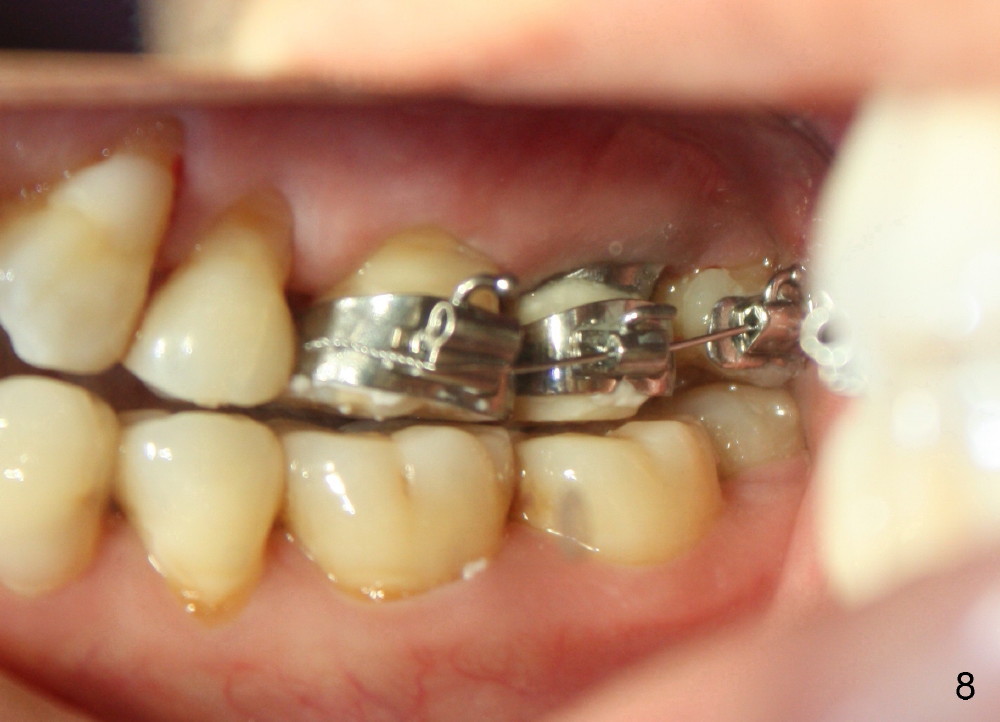

A 48-year-old lady is a dental phobic and has generalized chronic periodontitis. Bone loss around the tooth #2 has been severe for the last 5 years (Fig.1,2 *). Finally she agrees to have #2 (symptomatic) extracted and immediate implant placed (Fig.3 I). A 7x17 mm implant has to be used to achieve primary stability. The remaining buccal and lingual gaps are filled with allograft and membrane (Fig.4 *). Fig.5 shows that there is a space between the tooth #1 (asymptomatic) and the immediate implant (I). The wound/socket is protected by applying perio dressing around an abutment (Fig.6 A). Postop the patient is pain free; the perio dressing dislodges by itself. She returns 3.5 months later for restoration; but the tooth #1 has shifted mesially (Fig.6 arrow). The patient is not so willing to have #1 removed. Bands and bracket are placed in the neighboring teeth including a provisional crown to move the shifted tooth (with mobility) distally (Fig.7,9). The 2nd reason for #1 shifting is abnormal occlsual scheme on the right posterior region (Fig.8); mobility of #1 is the 1st one. The 3rd one is probably bruxism. In 5-6 weeks, the tooth #1 has moved to a desirable position (Fig.10, as compared to Fig.3,5). There is enough space for restoration (Fig.11,12).